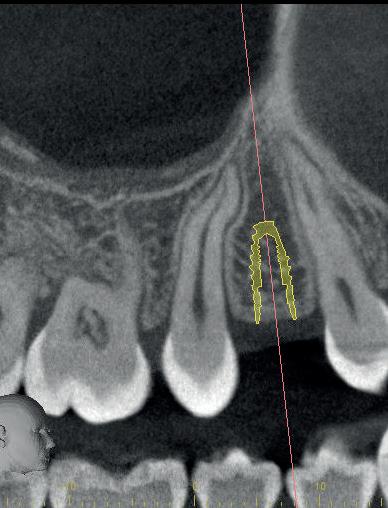

Voordat je aan een wortelkanaalbehandeling begint, zorg je voor (of maak je) een goede beginfoto waar het te behandelen gebitselement volledig op staat afgebeeld. Deze foto geeft essentiële informatie: de grootte van de pulpakamer en de ligging ervan; het aantal en de vorm van de wortels en de breedte van hun wortelkanalen en de lengte van de wortels. Hiermee kan je de DETI-score bepalen en de moeilijkheidsgraad inschatten. De grootte en de ligging van de pulpakamer op de röntgenfoto in combinatie met de ideale anatomische vorm, zoals in foto 1 is aangegeven, bepaalt de uiteindelijke vormgeving van de opening. Bij de molaren liggen de kanaalingangen in de buurt van de knobbeltoppen. Als die niet meer in originele staat

1. De locatie van de kanaalingangen ten opzichte van de occlusale morfologie (rood). In zwart is de ideale of standaard opening ingetekend. De uiteindelijke vorm van de opening is voorts ook afhankelijk van de klinische situatie, die vooral vanuit een goede begin foto wordt verkregen.

In dit geval heb ik mijn collega die belde voor advies, geadviseerd om contact op te nemen met de implantoloog waar ze mee samenwerkt. De kans dat implantologie op termijn nodig zal zijn, is namelijk heel erg groot. De patiënt kon dezelfde dag nog terecht bij tandarts-implantoloog Tristan Staas. Naast de aanwezige solo is er een CBCT gemaakt (foto 5 en 6). De behandelmogelijkheden zijn hierna uitgebreid besproken.

6. Screenshot van de CBCT.